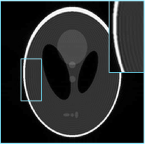

Refer to caption

(a) Validation curves

(b) Testing results

Figure 1: The performance comparison between several SISR models on proton density (PD) volumes of IXI dataset for SR×\times2. (a) The validation results on 6 PD volumes (576 2D slices). (b) The test results vs. the number of model parameters on 70 PD volumes (6720 2D slices, Bicubic: 35.04 dB). The symbols \vartriangle, \square, and \circ represent models with less than 1M, 10M, 20M and more than 20M parameters respectively. C1 indicates that the training sample is a single slice, and C96 indicates that the model treats 96 slices of a 3D volume as 96 channels.